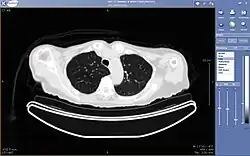

Typically a PACS consists of a multitude of devices. The first step in typical PACS systems is the modality. Modalities are typically computed tomography (CT), ultrasound, nuclear medicine, positron emission tomography (PET), and magnetic resonance imaging (MRI). Depending on the facility's workflow most modalities send to a quality assurance (QA) workstation or sometimes called a PACS gateway. The QA workstation is a checkpoint to make sure patient demographics are correct as well as other important attributes of a study. If the study information is correct the images are passed to the archive for storage. The central storage device (archive) stores images and in some cases reports, measurements and other information that resides with the images. The next step in the PACS workflow is the reading workstations. The reading workstation is where the radiologist reviews the patient's study and formulates their diagnosis. Normally tied to the reading workstation is a reporting package that assists the radiologist with dictating the final report. Reporting software is optional and there are various ways in which doctors prefer to dictate their report. Ancillary to the workflow mentioned, there is normally CD/DVD authoring software used to burn patient studies for distribution to patients or referring physicians. The diagram above shows a typical workflow in most imaging centers and hospitals. Note that this section does not cover integration to a Radiology Information System, Hospital Information System and other such front-end system that relates to the PACS workflow.

More and more PACS include web-based interfaces to utilize the internet or a wide area network (WAN) as their means of communication, usually via VPN (Virtual Private Network) or SSL (Secure Sockets Layer). The clients side software may use ActiveX, JavaScript and/or a Java Applet. More robust PACS clients are full applications which can utilize the full resources of the computer they are executing on and are unaffected by the frequent unattended Web Browser and Java updates. As the need for distribution of images and reports becomes more widespread there is a push for PACS systems to support DICOM part 18 of the DICOM standard. Web Access to DICOM Objects (WADO) creates the necessary standard to expose images and reports over the web through truly portable medium. Without stepping outside the focus of the PACS architecture, WADO becomes the solution to cross platform capability and can increase the distribution of images and reports to referring physicians and patients.